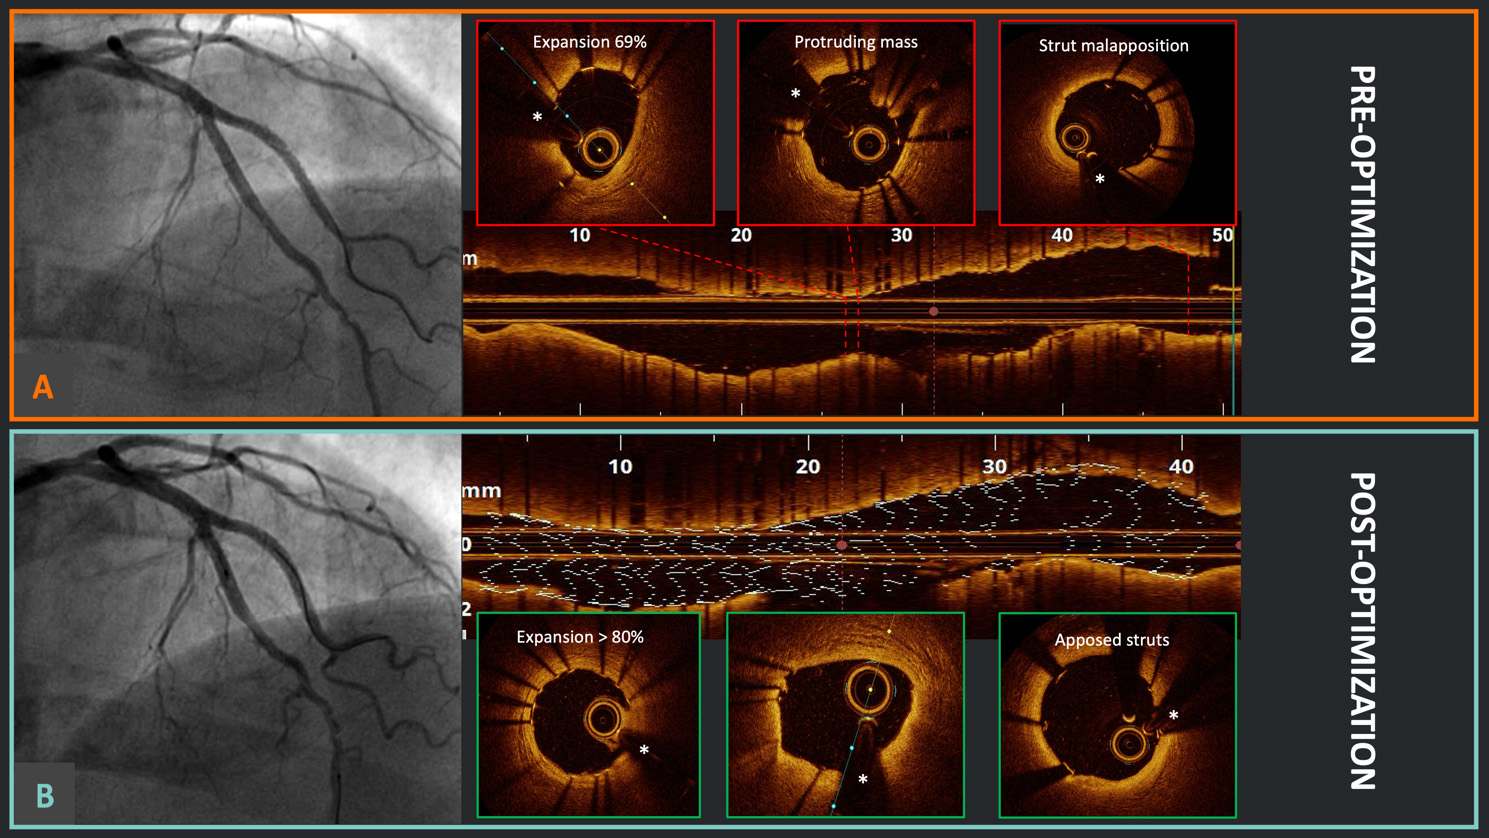

In the spectrum of IVI, two essential modalities are available: IVUS and OCT, each with distinct principles and technical specifications. IVUS is based on the propagation and reflection of high-frequency sound waves within coronary vessels to generate cross-sectional images. The first phased-array IVUS catheters were introduced in the clinical field in the early 1990s, with low-resolution imaging (20–40 MHz, 100–200 µm axial resolution). More recently, high-frequency (up to 65 MHz) and dual-frequency catheters (35/65 MHz), developed using asymmetric electrodes for improved beam profiles, have been introduced, allowing higher-resolution quality imaging (22–40 µm axial resolution) while maintaining deep tissue penetration [15]. Conversely, OCT operates on the principles of low-coherence interferometry, employing near-infrared light-emitting catheters that typically work with wavelengths around 1300 nm. These beams of light diverge into two arms: one directed toward the coronary tissue under examination (the sample arm) and another toward a reference mirror (the reference arm). Light reflected from both the sample and reference arms recombines, creating an interference pattern. OCT measures the interference pattern to construct detailed cross-sectional images. This pattern is highly sensitive to variations in the path length of the reflected light, allowing OCT to achieve an exceptional resolution [16, 17]. However, due to their technical specificities and differences in clinical practice, their application does not completely overlap [18]. IVUS offers a superior penetration depth, especially relevant in large vessels (e.g., the left main), and is instrumental in characterizing coronary wall remodeling secondary to CAD progression (i.e., positive vs. negative remodeling). Since no additional administration of contrast is necessary, IVUS can be crucial for assessing and treating spontaneous coronary artery dissections in cases of uncertain angiographic diagnosis [19] or for navigating and wiring the intra- and extraluminal spaces in cases of chronic total occlusions [20, 21]. Finally, IVUS can be an exceptional tool to achieve optimal results in patients with severe renal dysfunction and complex lesions that require intervention [22]. OCT stands out with its exceptional resolution, enabling the precise assessment of microstructures within the coronary vessel wall, which is crucial for evaluating plaque vulnerability, macrophage infiltration, and detecting the most subtle intimal disruptions [23]. Moreover, in cases of a high calcium burden, OCT allows a more precise analysis of plaque distribution and differentiation [24]. Finally, the detailed visualization of coronary stents, whether immediately after implantation or at longer-term follow-up, precise stent optimization during PCI, and the assessment of strut coverage and stent failure at follow-up are specific applications where OCT can be of great benefit [25, 26]. An example of OCT-guided stent optimization is presented in Fig. 1. A technical comparison between current-generation IVUS and OCT systems, along with respective potential advantages in different clinical settings, is shown in Table 1.

Fig. 1. Optical coherence tomography (OCT)-guided percutaneous coronary intervention (PCI) optimization. (A) Good angiographic result after double kissing crush technique for a left anterior descending artery and diagonal branch bifurcation in the Optical Coherence Tomography Optimized Bifurcation Event Reduction (OCTOBER) study; meanwhile, the OCT pullback identified the presence of stent underexpansion, a protruding mass (likely calcium), and relevant proximal strut malapposition. (B) After OCT-guided optimization, there was no significant angiographic difference; however, at OCT, it is evident that the stent underexpansion has been successfully corrected, with no protruding masses and appropriate strut apposition proximally. *Wire artifact.